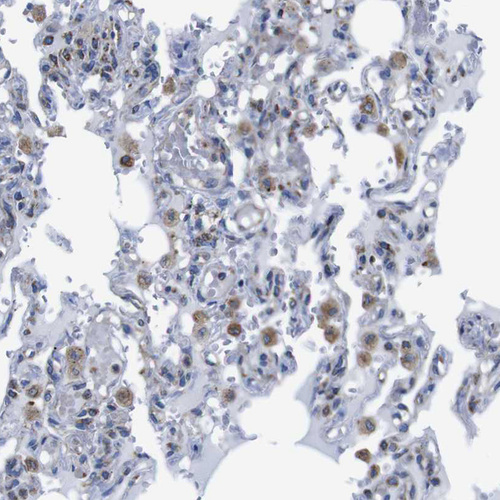

Immunohistochemical staining of human lung shows moderate cytoplasmic positivity.